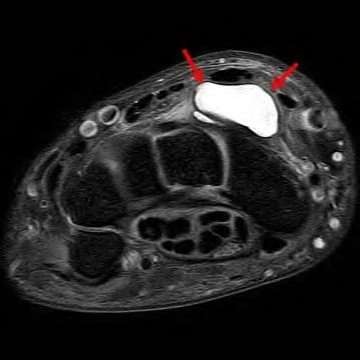

Question 9:

A 30-year-old male sustains a severe midfoot sprain. Radiographs reveal widening between the bases of the first and second metatarsals. The primary ligamentous stabilizer disrupted in this classic Lisfranc injury connects which two osseous structures?

Correct Answer: Medial cuneiform to 2nd metatarsal base

Explanation:

The Lisfranc ligament is the strongest ligament in the tarsometatarsal joint complex. It courses obliquely from the lateral aspect of the medial cuneiform to the medial base of the second metatarsal. It acts as the primary stabilizer of the second metatarsal base. Disruption results in the classic widening between the first and second rays, often with an avulsion fragment ('fleck sign').